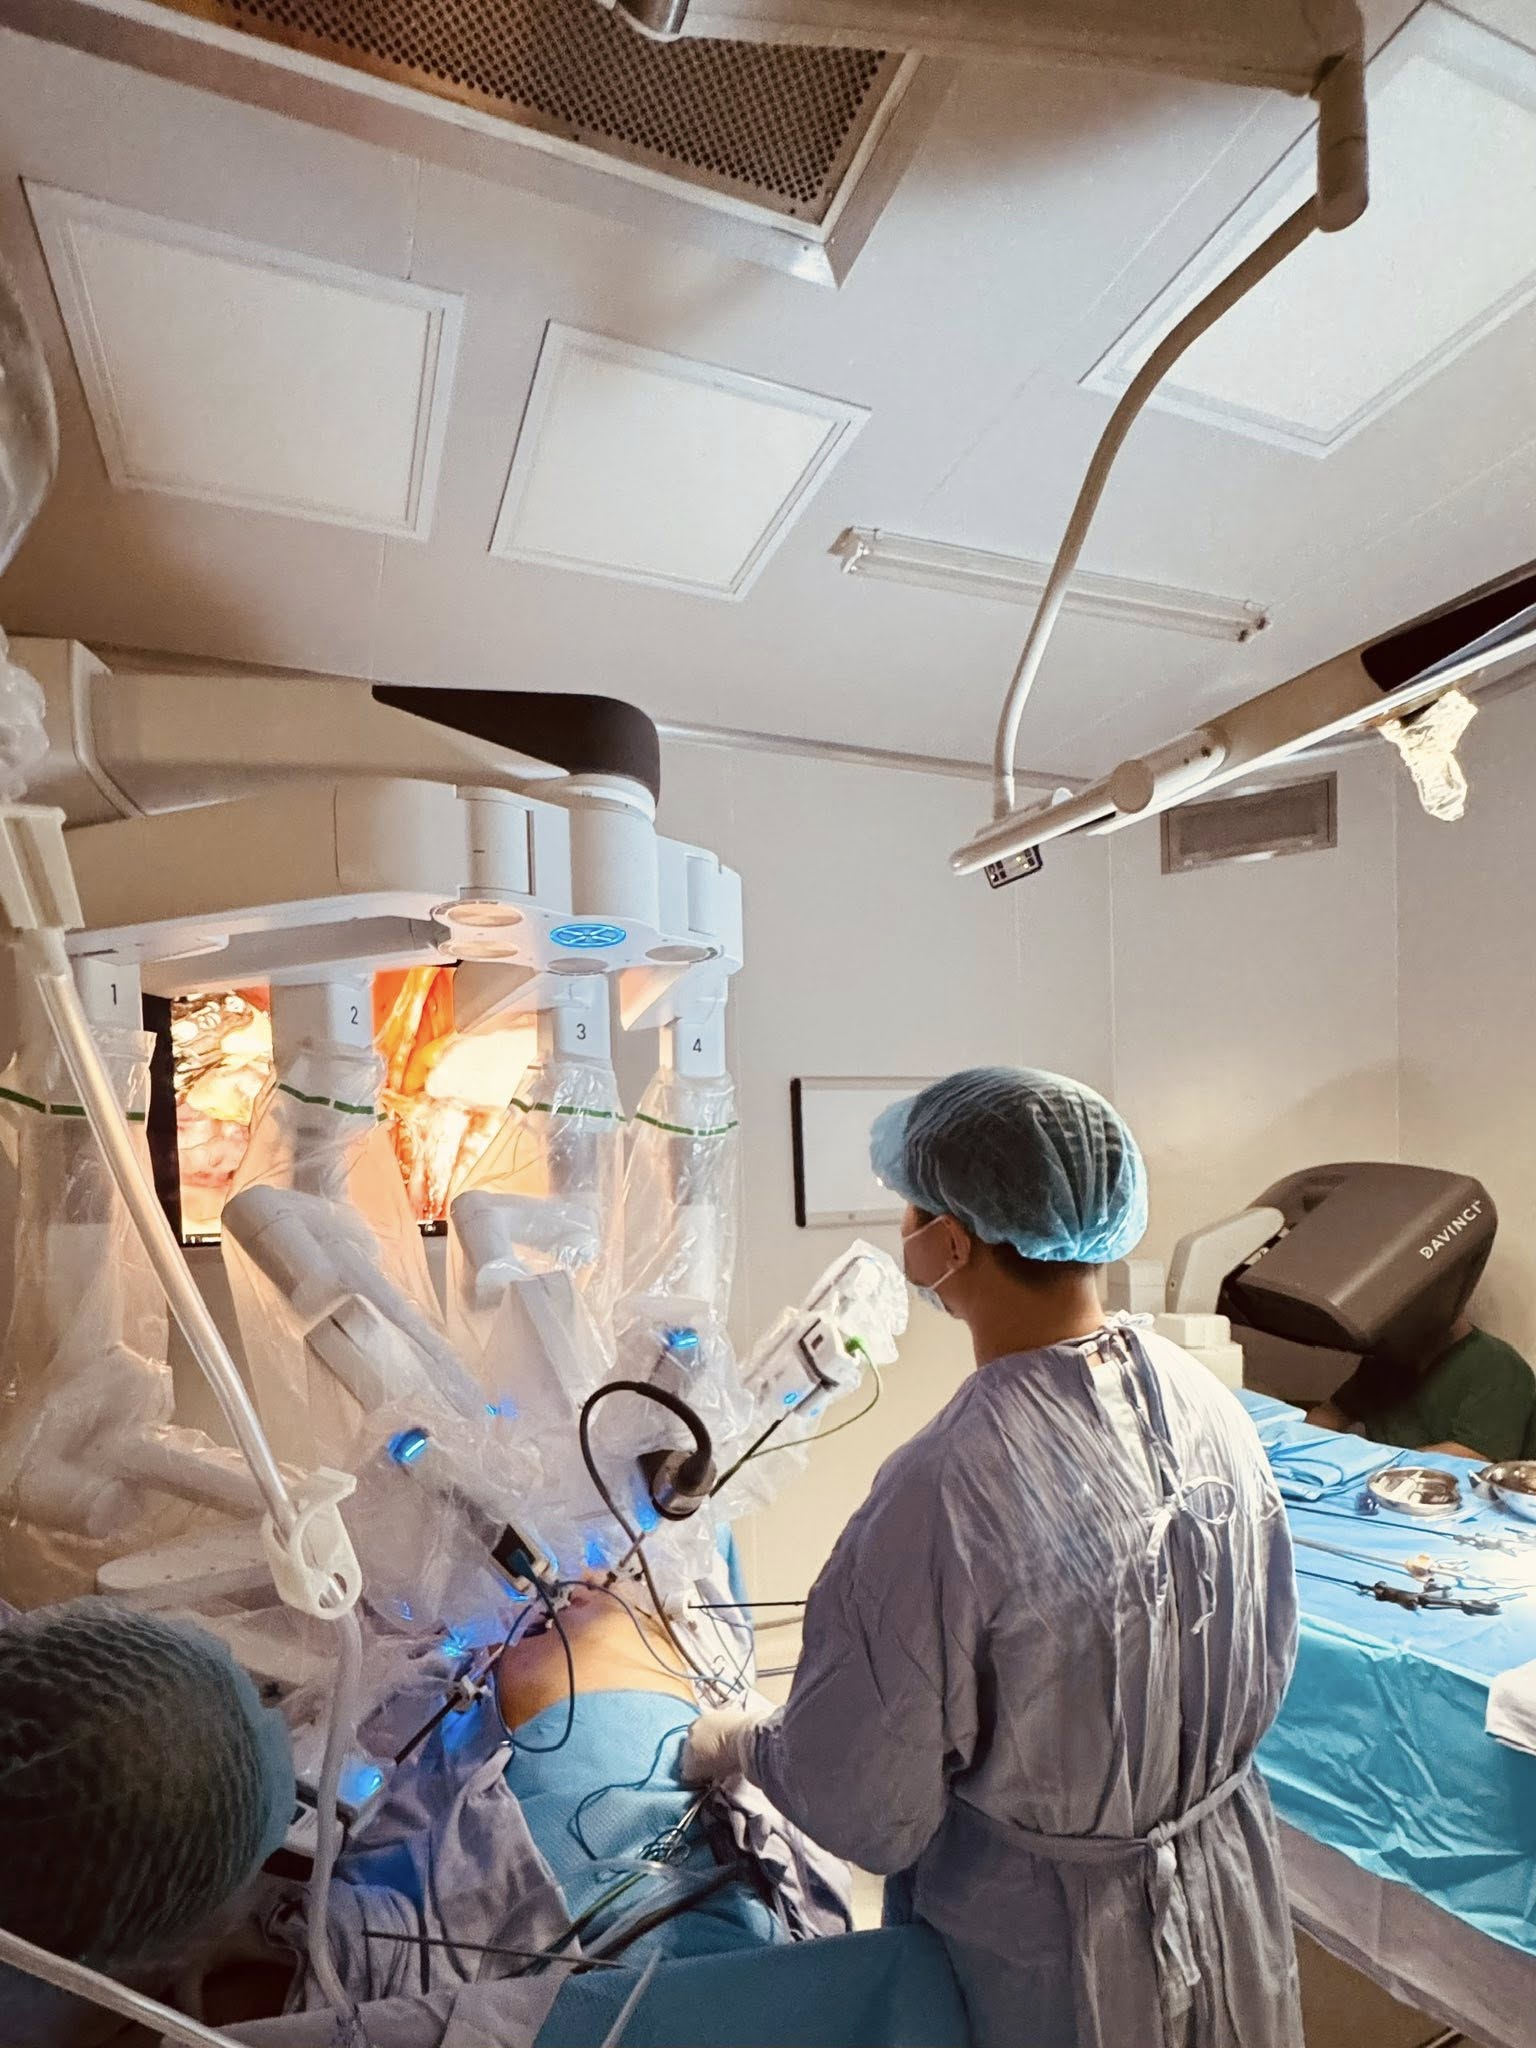

Các cánh tay robot Da Vinci Xi liên tục bóc tách và khâu nối, giúp bác sĩ cắt trọn khối u và tạo hình bàng quang từ ruột non cho người đàn ông bị ung thư.

Trên màn hình phóng đại độ nét cao, từng cấu trúc nhỏ trong vùng chậu hiện rõ. TS.BS Nguyễn Hoàng Đức, Trưởng khoa Tiết niệu, Trung tâm Tiết niệu – Thận học – Nam khoa, Bệnh viện Đa khoa Tâm Anh TP HCM đang điều khiển robot Da Vinci Xi bóc tách khối u đã xâm lấn cơ bàng quang và nạo vét hạch chậu cho ông Toàn, 54 tuổi.

Bác sĩ Đức đang điều khiển robot Da Vinci Xi phẫu thuật cắt khối u và tạo bàng quang mới cho người bệnh. Ảnh: Bệnh viện Đa khoa Tâm Anh

Bác sĩ Đức đang điều khiển robot Da Vinci Xi phẫu thuật cắt khối u và tạo bàng quang mới cho người bệnh. Ảnh: Bệnh viện Đa khoa Tâm Anh

Những cánh tay robot với khớp nối linh hoạt xoay 540 độ được đưa vào khoang bụng bệnh nhân qua những lỗ nhỏ chỉ 1 cm. Bác sĩ Đức điều khiển robot Da Vinci Xi cắt trọn tận gốc bàng quang và nạo vét hạch chậu cho ông Toàn, bảo toàn các cấu trúc thần kinh.